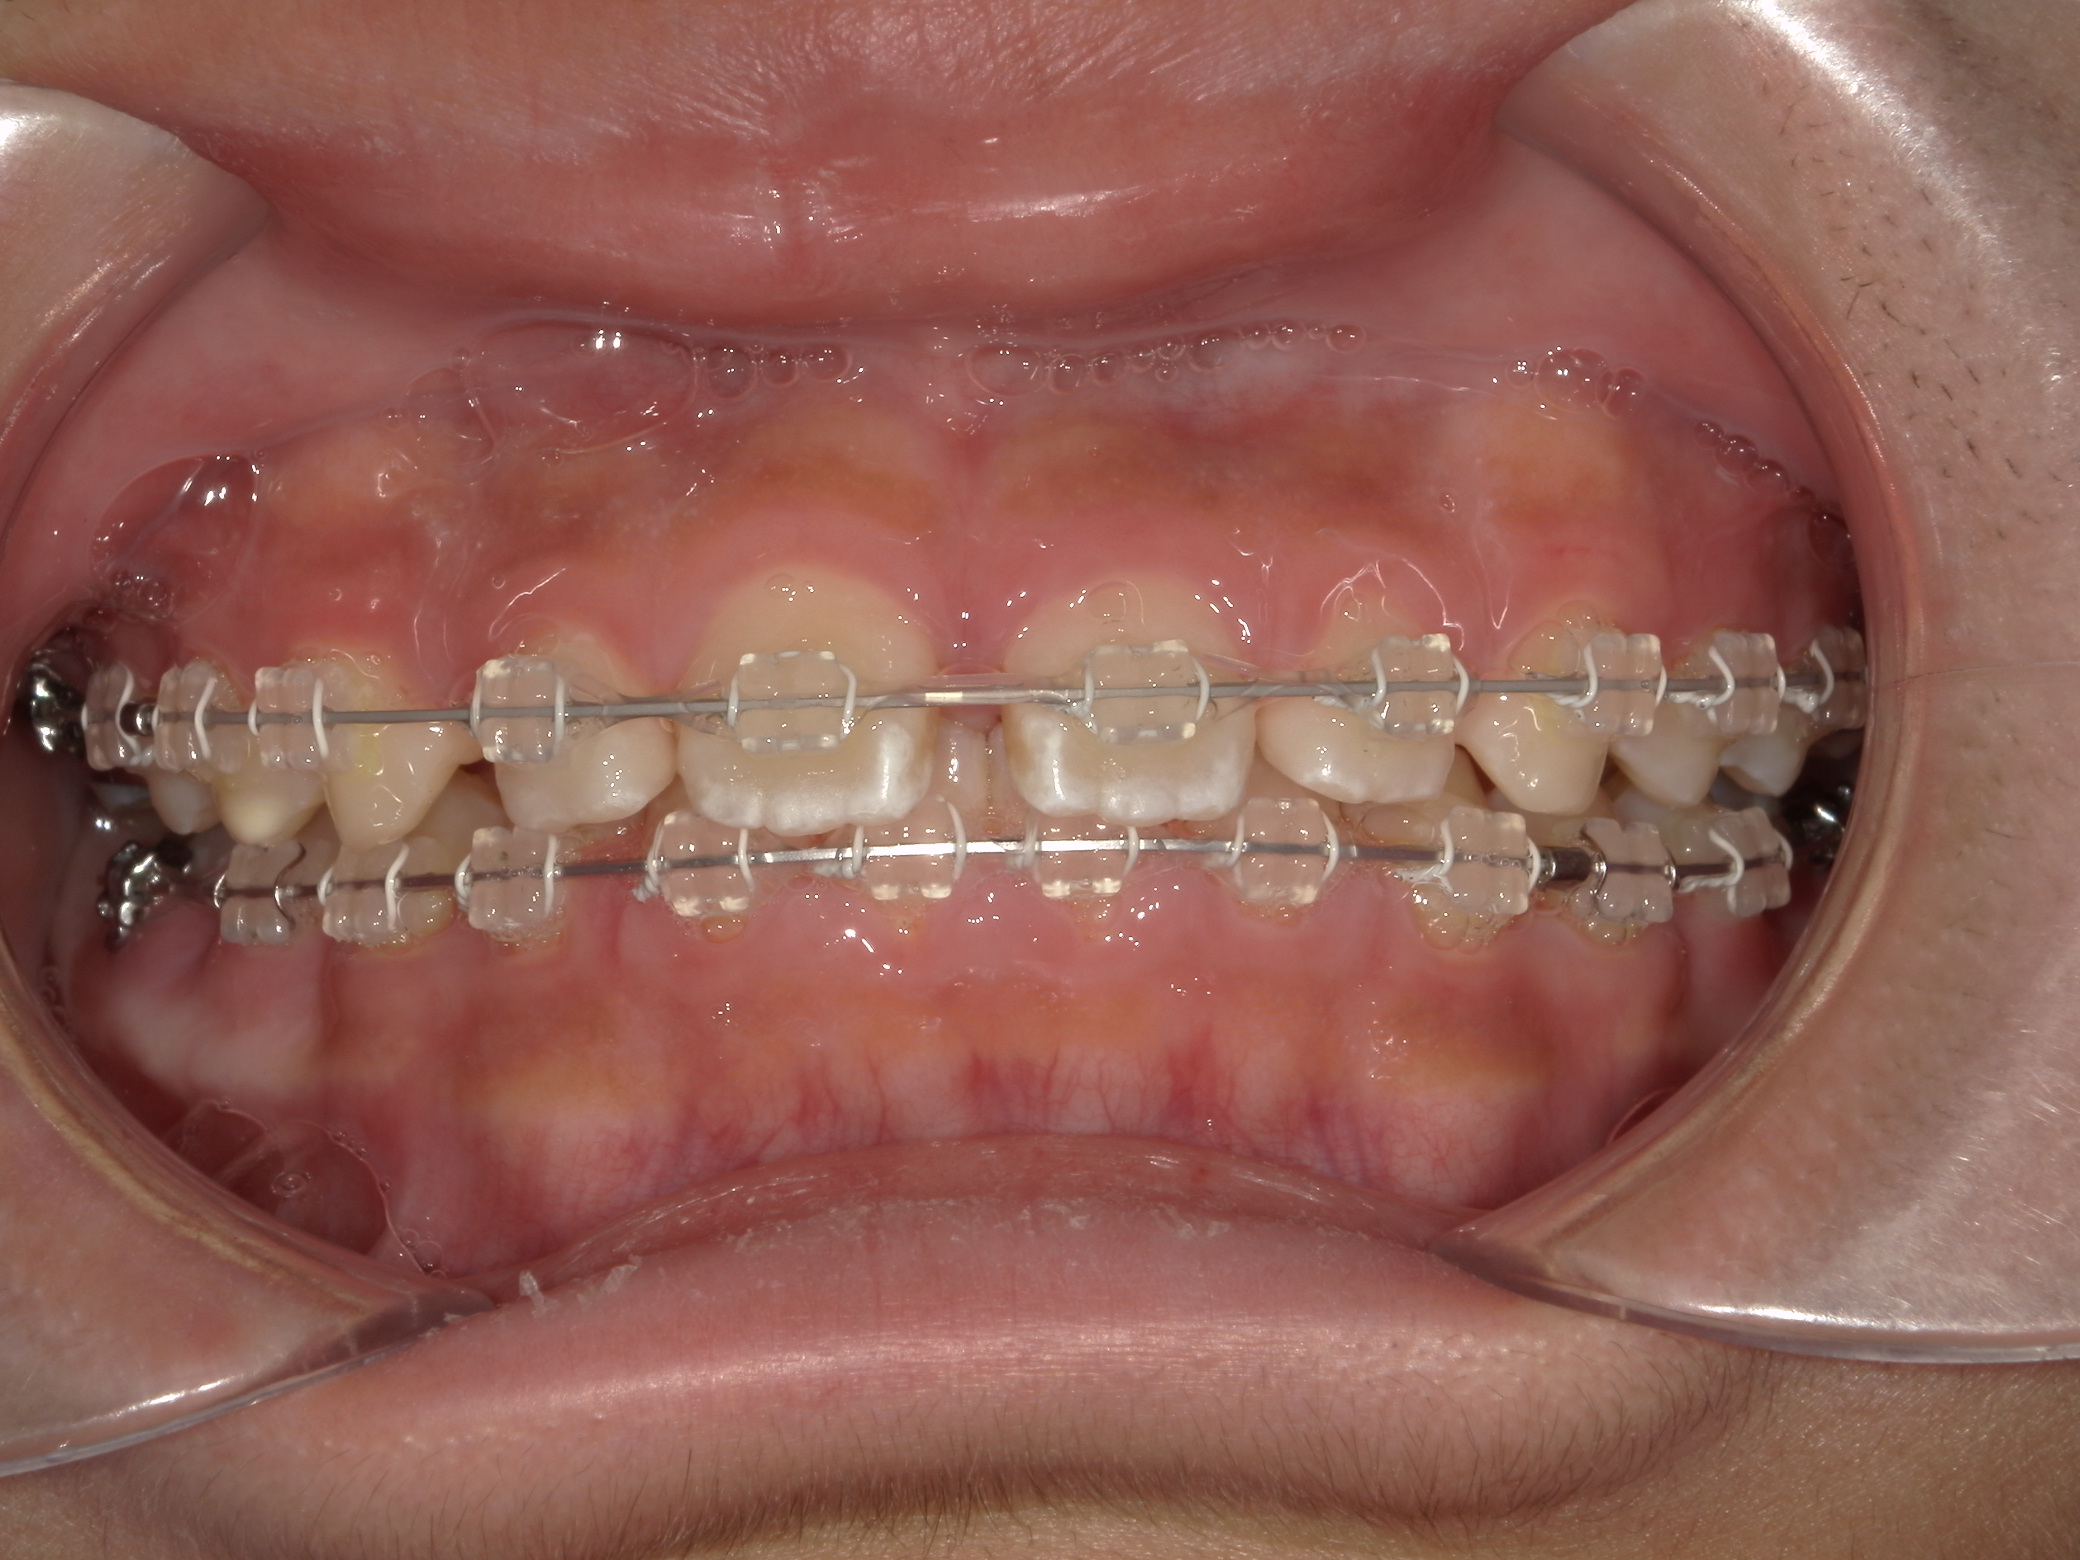

すきっ歯(11歳空隙歯列)

11歳 男性

非抜歯矯正治療

表側ワイヤー矯正

使用装置写真

935,000円(税込)

1年2か月

隙間が歯列全体にあり、かみ合わせも深い状態でした。

上下にワイヤーを装着し、かみ合わせをあげながら隙間を閉じています。

副作用:歯根吸収・歯髄壊死・歯肉退縮・隙間の再発